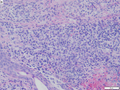

| Cutaneous T-cell lymphoma (includes mycosis fungoides) | single lymphocytes in epidermis ("lymphocyte exocytosis") | lymphocyte nests in the epidermis ("Pautrier microabscesses"), short arrays of lymphocytes along the basal layer of the epidermis ("epidermotropism") | Clinical | CD45, CD4 | B cell lymphoma (?) | Other | |